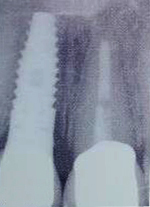

Este stiinta care se ocupa cu diagnosticul, inserarea, restaurarea si utilizarea structurilor orale, aloplastice sau autogene pentru refacerea structurilor morfofunctionale ale aparatului dento-maxilar.

Protetica pe implante este ramura implantologiei care se ocupa de faza restaurativa si componentelor planului general de tratament dupa inserarea implantelor.

Implantele dentare reprezinta la ora actuala singura posibilitate de a inlocui dintii lipsa prin protezare fixa rezultand o dentitie foarte apropiata de dintii naturali. Implantele dentare sunt niste radacini artificiale realizate din titan care se insera in os. Dupa o perioada de aproximativ 6 luni perioada necesara pentru integrarea implantului, acestuia i se ataseaza un bont protetic pe care ulterior se fixeaza coronita de ceramica sau proteza.